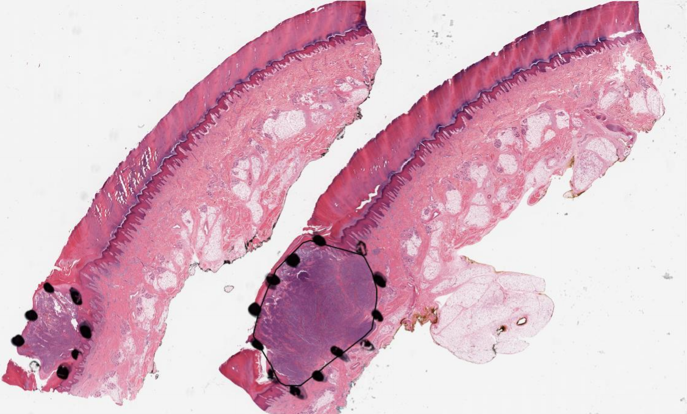

2.3 Model training and assessment

Training patch classifier. A three-class patch classification model (PCLA-3C) was trained on the labeled patches with VGG16 [31] as base architecture (Fig. 2d). Models were trained using this CNN architecture and by backpropagation, we manually changed the last layer’s parameters to optimize the model. The patch classifier would return a WSI with three key scores, corresponding to three categories (melanoma, nevus and other). Slide classification and ROI detection. In the testing stage, all patches from a WSI were first fed into the trained patch classifier. Ignoring patches predicted as other, slide-level prediction was done by majority vote based on patches predicted as melanoma and nevus. If the number of patches labeled as melanoma exceeded the number of patches labeled as nevus in one WSI, we classified it as melanoma, and vice versa (Fig. 2e). For a WSI classified as melanoma, all the patches from this slide will be ranked by melanoma predicted scores. Otherwise, all the patches will be ranked by nevus predicted scores (Fig. 2f). Model assessment. To evaluate the performance of ROI detection, the annotated ratio was measured to calculate Intersection over Union (IoU) for each slide. Given a slide, annotated ratio was calculated by the number of patches in the annotated region divided by the number of patches extracted from the slide: ,where is the number of patches in A (annotated region) and is the number of patches in C (WSI). Then, the top patches based on predicted scores were classified as ROI, where was the total number of patches from a slide. For example, if for a slide in the testing set, it means that 20% of the regions in the slide are ROIs. Then, the model will predict the top 20% of patches (based on the predicted scores) as patches in the ROIs. The performance was measured by Intersection over Union (IoU), which compared the annotated region and predicted ROI region. Since the framework was patch-based, IoU was calculated by the number of patches in the intersection region (the region in both annotated and predicted regions) divided by the number of patches in the union of the annotated and predicted ROI regions: , where shows the number of patches in the region of and shows the number of patches in the region of . A is annotated region and B is the predicted/highlighted region. Visualization. The detection methods could provide three types of visualization maps: boundary, overlap and heatmap (examples were in Fig. 3). Three visualization maps will be generated based on the predicted scores calculated in the ROI detection section (Fig. 2g). The overlap map highlighted top-ranked patches in a WSI and masks other areas with a transparent blue color (Fig. 3a, 3d). The percentage of highlighted patches equaled (the annotated ratio). Therefore, the highlighted region was also the predicted ROI. The boundary map showed the boundary of the largest ROI cluster based on the highlighted patches, where the highlighted patches were clustered by OPTICS algorithm [1] (Fig. 3b, 3e). The last one was a heatmap where red covered regions that had high predicted scores and blue covered regions that had low predicted scores (Fig. 3c, 3f).

(a) Boundary

(b) Overlay

(c) Heatmap

(d) Boundary

(e) Overlay

(f) Heatmap